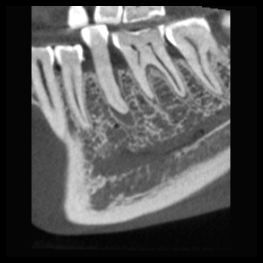

Rozdzielczość HD przy ultraniskiej dawce

wielkość woksela 150 μm, dawka pacjenta ~32 μSv

Duża szczegółowość, średnia dawka